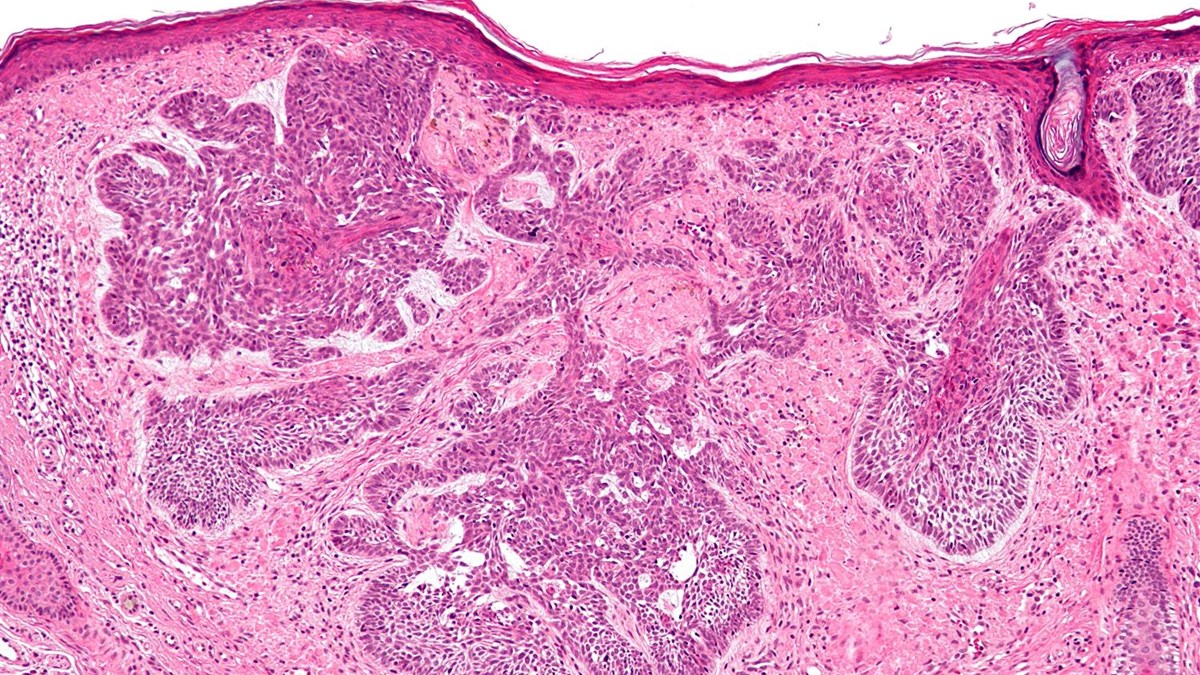

BCAC can be divided into four types based on growth pattern when examined under the microscope: solid, trabecular, tubular, and membranous; of these, the solid type is the most common (4). BCAC is difficult to diagnose as it is very similar to other salivary gland cancers, including basal cell adenoma. BCAC is distinguished from basal cell adenoma by its entanglement with surrounding nerves and blood vessels (1). A combination of methods is used for diagnosis, including biopsy and imaging techniques such as magnetic resonance imaging (MRI) and ultrasound (5).

Image credit: Courtesy of Professor Ali Khurram